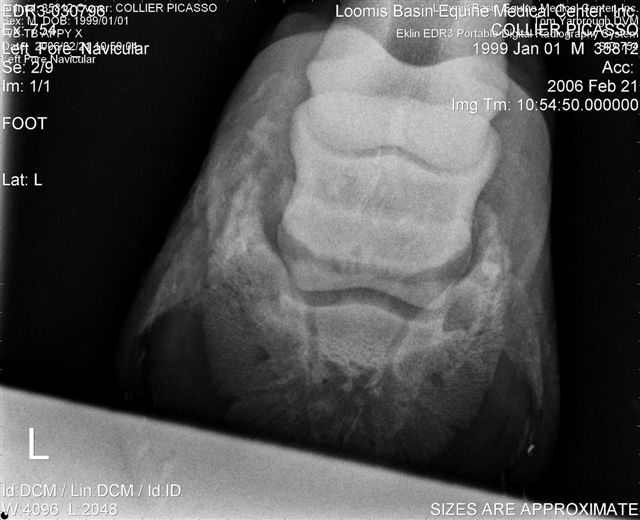

Let's label the radiographs from left to right with numbers. The abnormalities I see on the L using the photo's number as reference:

1) Odd lucency (darker) at the top/lateral margin of the coffin bone (seen in many images). It would interesting if this is also the site of the odd bruising.

2) Decrease lucency (darker) in the body of the navicular bone.

2) Remarkable cone shape areas of decrease lucency (darker) along the distal margin of the navicular bone.

3) Assymetrical flexor surface of the navicular bone.

4) There is the appearance of poor ap balance of the foot with the heels being low

4) Soles appear thin

4) Small osteophyte (bone spur) on the front margin of the pastern joint.

Unless there is something I am missing in the images the extensor process appears to have healed well on the L. The significance of each of these lesions will depend on clinical findings Ann and confirmation that these are actual lesions and not artifacts created by positioning or the foot preparation for radiography. You should note I am not a radiologist and that viewing images in this manner is not as revealing as viewing the radiographs first hand.

The lateral aspect of the wing is somewhat misshapen, perhaps the old fracture?